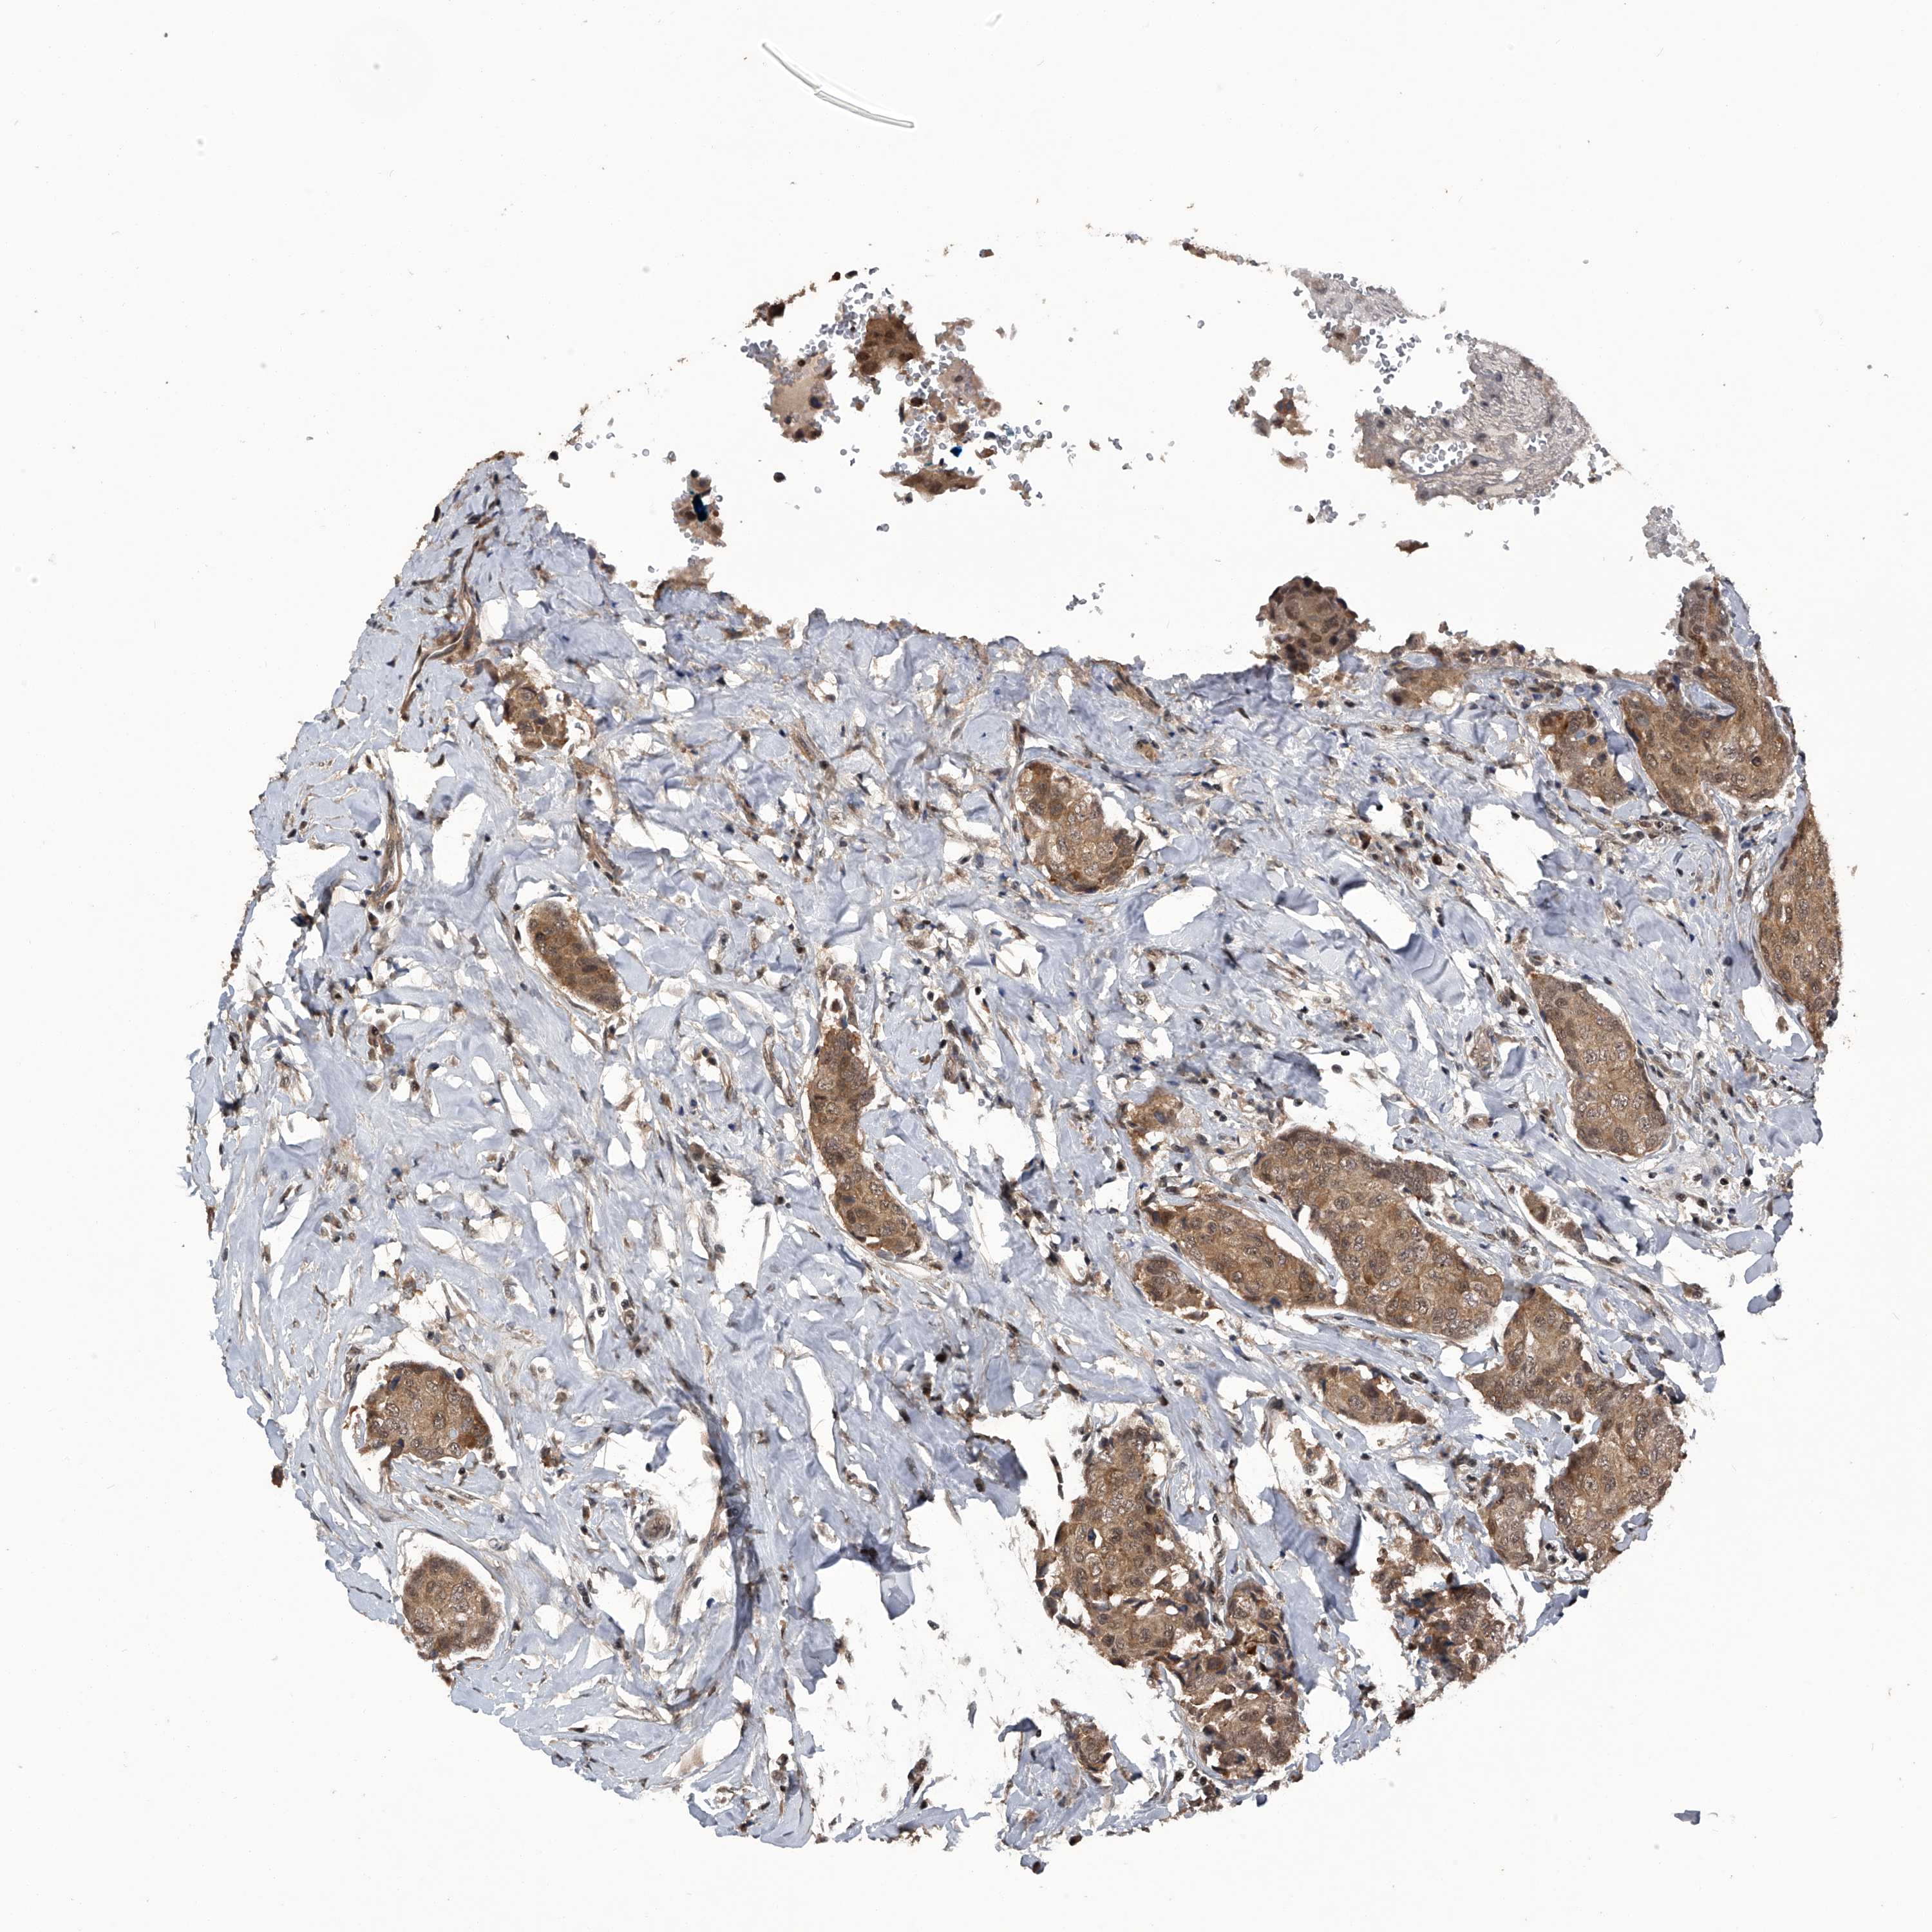

CANCER BREAST CANCER Show tissue menu

BRCA TCGA BRCA VALIDATION PROTEIN EXPRESSION